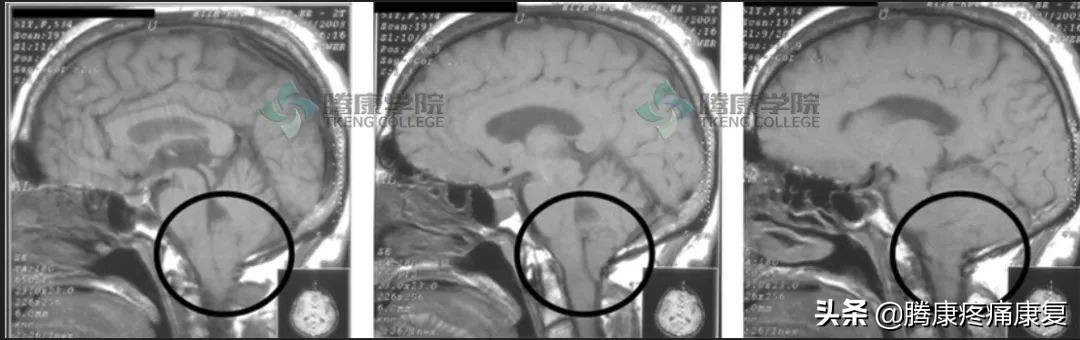

颈椎及其周围软组织的疾病也可能和紧张型头痛相似。Arnold- Chiari畸形与紧张型头痛表现相似,在后颅窝和颈椎MRI中可以轻易发现异常。